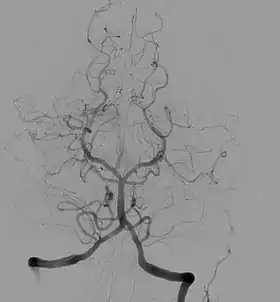

Cerebral Angiography

Introduced in 1927, cerebral angiography enabled doctors to accurately detect and diagnose anomalies in the brain such as tumors and internal carotid artery occlusions. Over the course of a year, Egas Moniz, the inventor of cerebral angiography, ran experiments with various dye solution percentages that were injected into arteries to help better visualize the blood vessels in the brain before discovering that a solution consisting of 25% sodium iodide was the safest for patients, as well as the most effective in the visualization of blood vessels and arteries within the brain.[7]